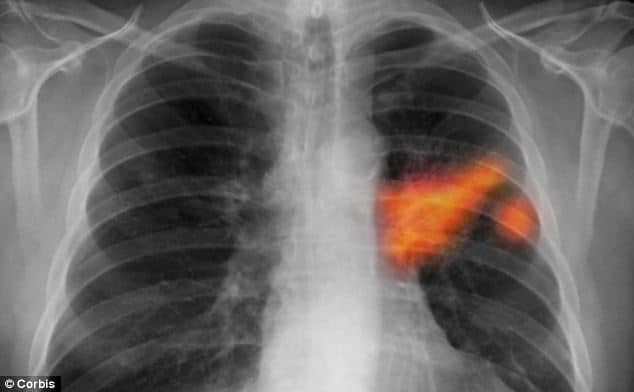

Cigarette smoke harms your body because it breaks down the structure of your lungs, and causes your airways to narrow, making breathing much more difficult.

Staying away from cigarette smoke is another good way to keep your heart and lungs healthy! Smoke from cigarettes lines your lungs with a thick layer of chemicals that reduces the ability of your lungs to inflate or deflate and to exchange oxygen and carbon dioxide.

Heart and lung disease is usually chronic, which means it develops slowly over a long period of time. These diseases are often associated with the common heart and lung disease symptoms which are shortness of breath and chest pain.